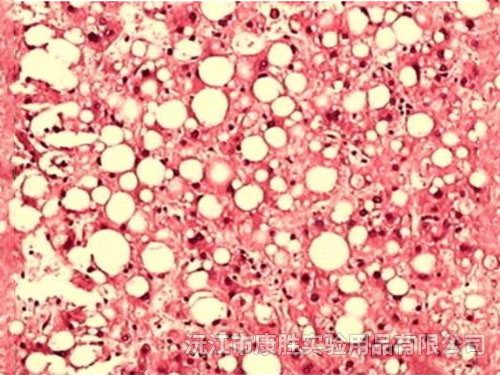

肝脂肪变性